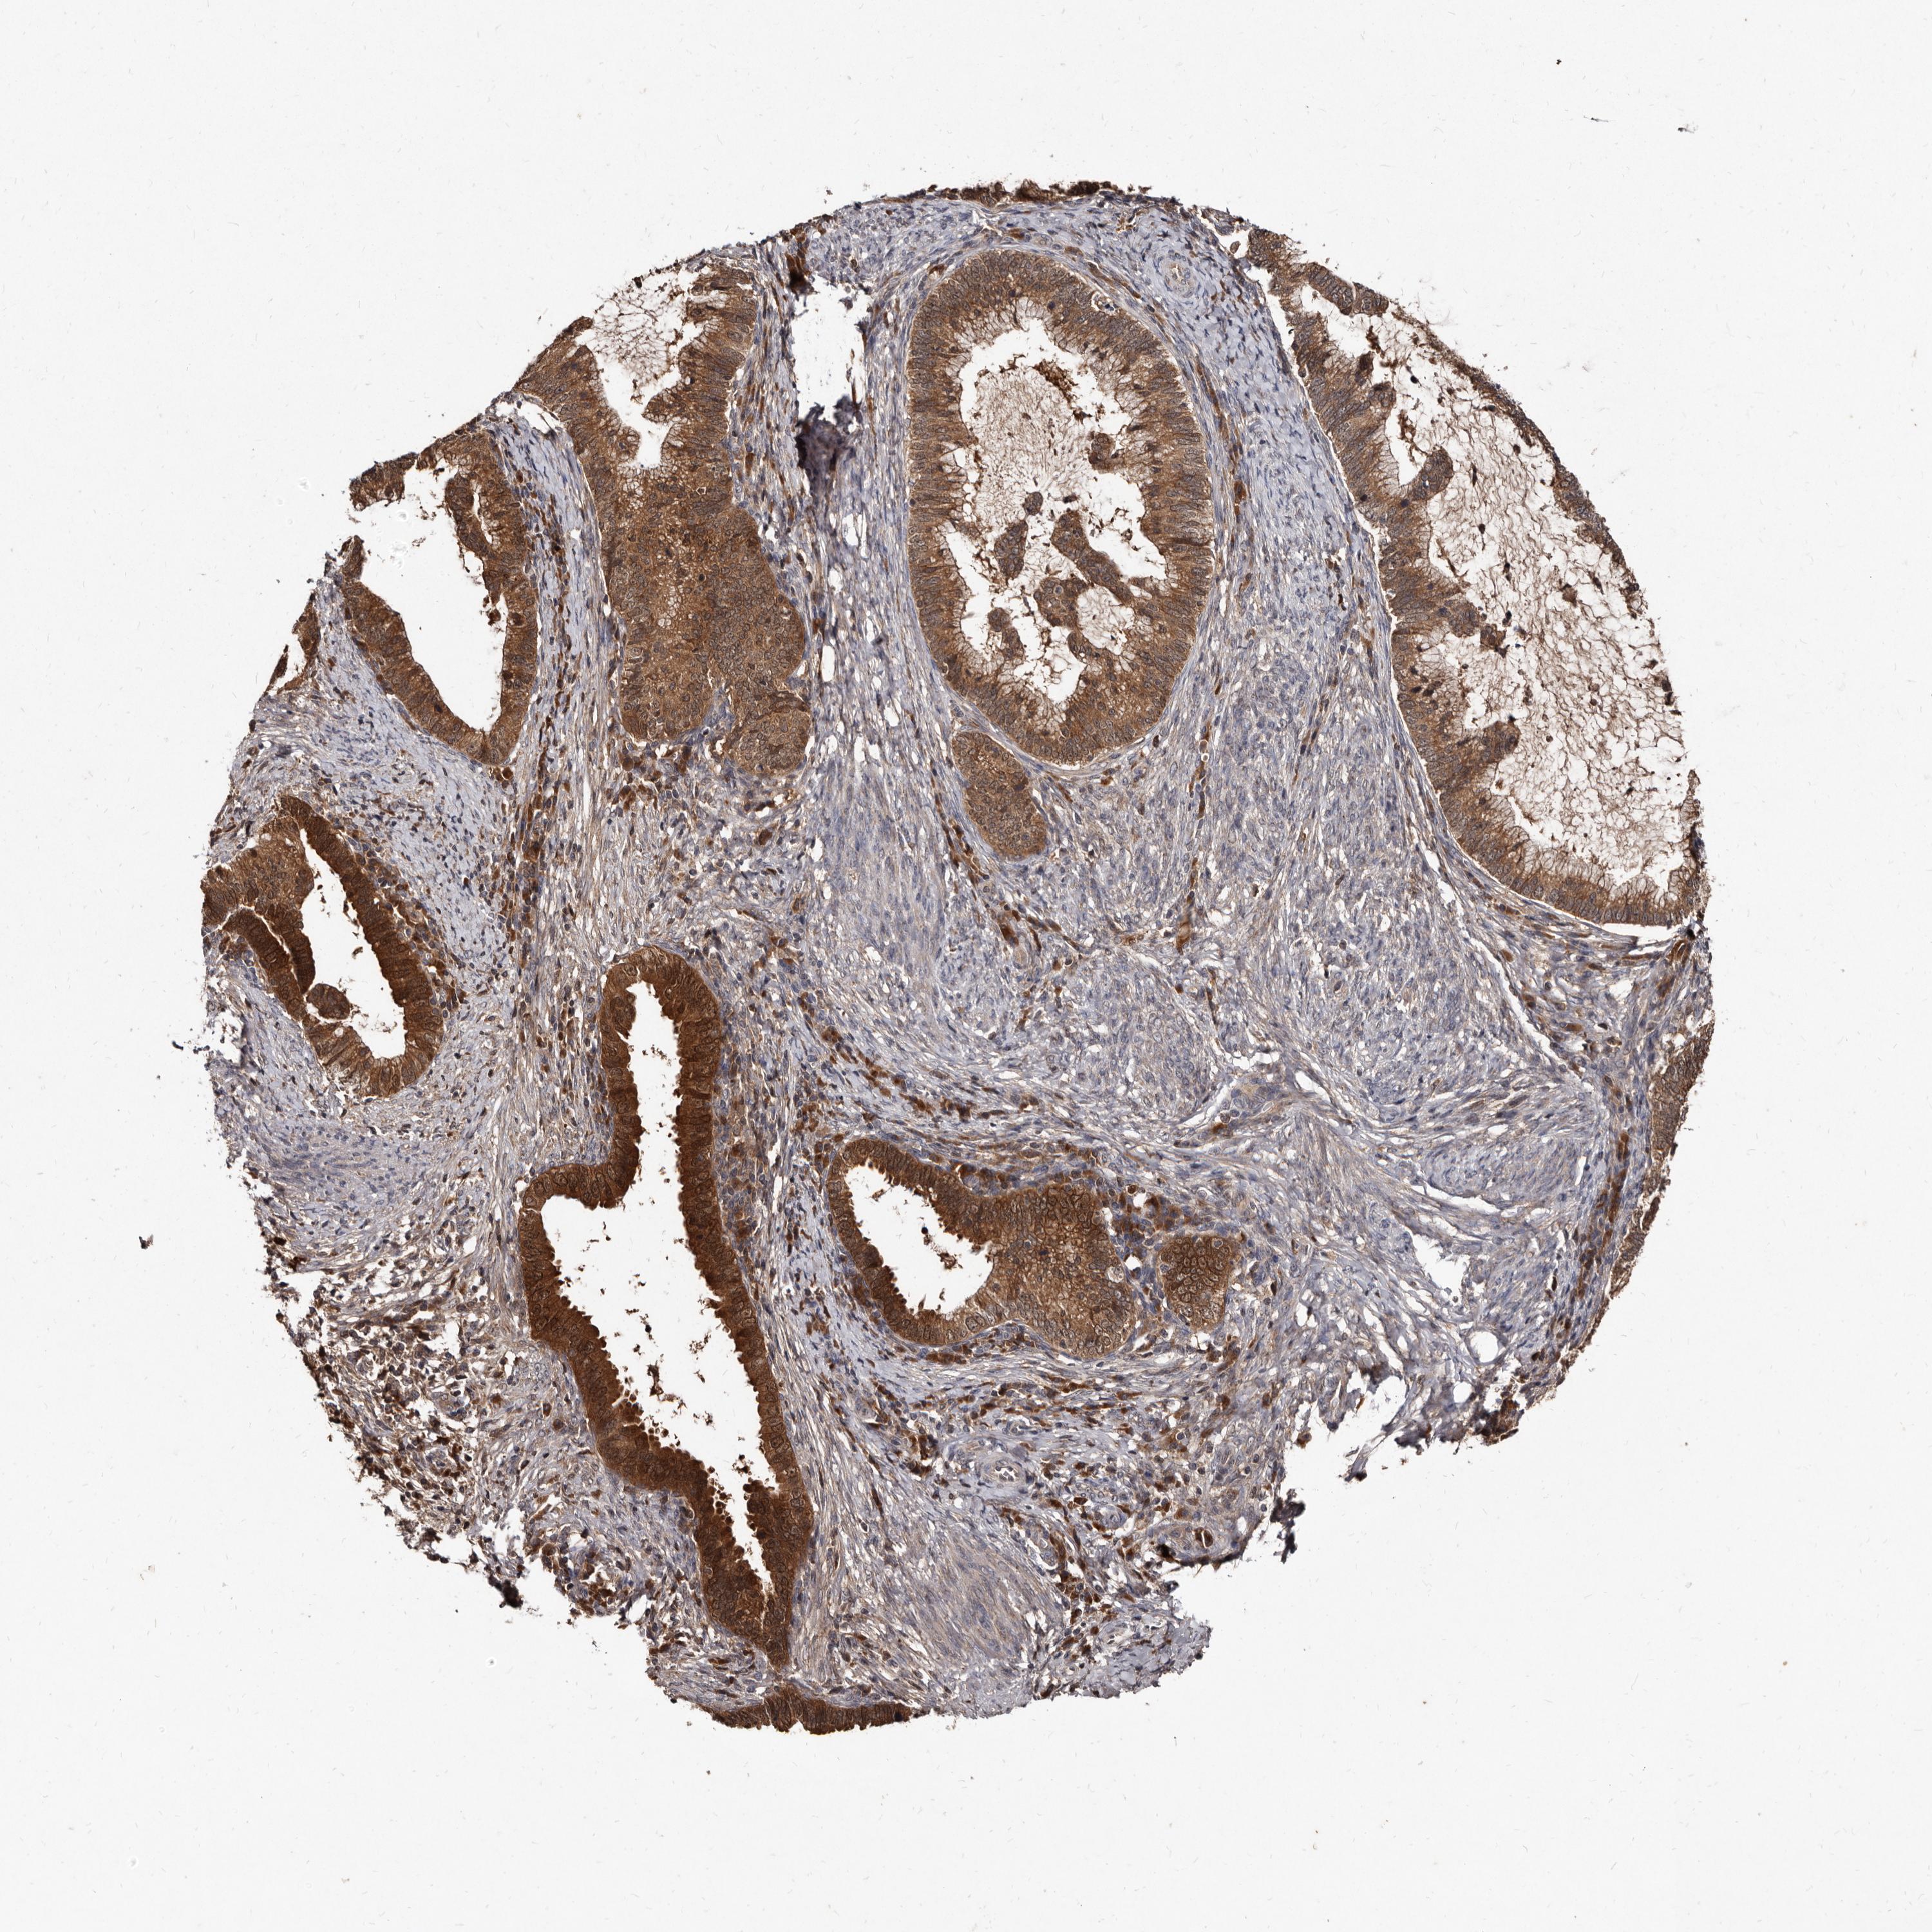

CERVICAL CANCER - Protein expressioni

A mouse-over function shows sample information and annotation data. Click on an image to view it in a full screen mode. Samples can be filtered based on level of antibody staining by selecting one or several of the following categories: high, medium, low and not detected. The assay and annotation is described here.

Note that samples used for immunohistochemistry by the Human Protein Atlas do not correspond to samples in the TCGA dataset.

Antibody stainingi

Antibody staining in the annotated cell types in the current human tissue is reported as not detected, low, medium, or high, based on conventional immunohistochemistry profiling in selected tissues. This score is based on the combination of the staining intensity and fraction of stained cells.

Each image is clickable and will lead to virtual microscopy that enables deeper exploration of all samples and also displays staining intensity scores, fraction scores and subcellular localization as well as patient and tissue information for each sample.

Antibody HPA029900

Staining

High

Medium

Low

Not detected

Intensity

Strong

Moderate

Weak

Negative

Quantity

>75%

75%-25%

<25%

None

Location

Nuclear

Cytoplasmic/membranous

Cytoplasmic/membranous,nuclear

Squamous cell carcinoma, NOS

Adenocarcinoma, NOS